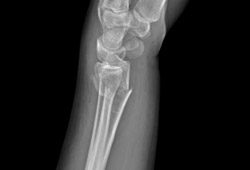

Type B (simple) intra-articular fracture of the distal radius: lateral view

From the collection of Dr Chaitanya S. Mudgal